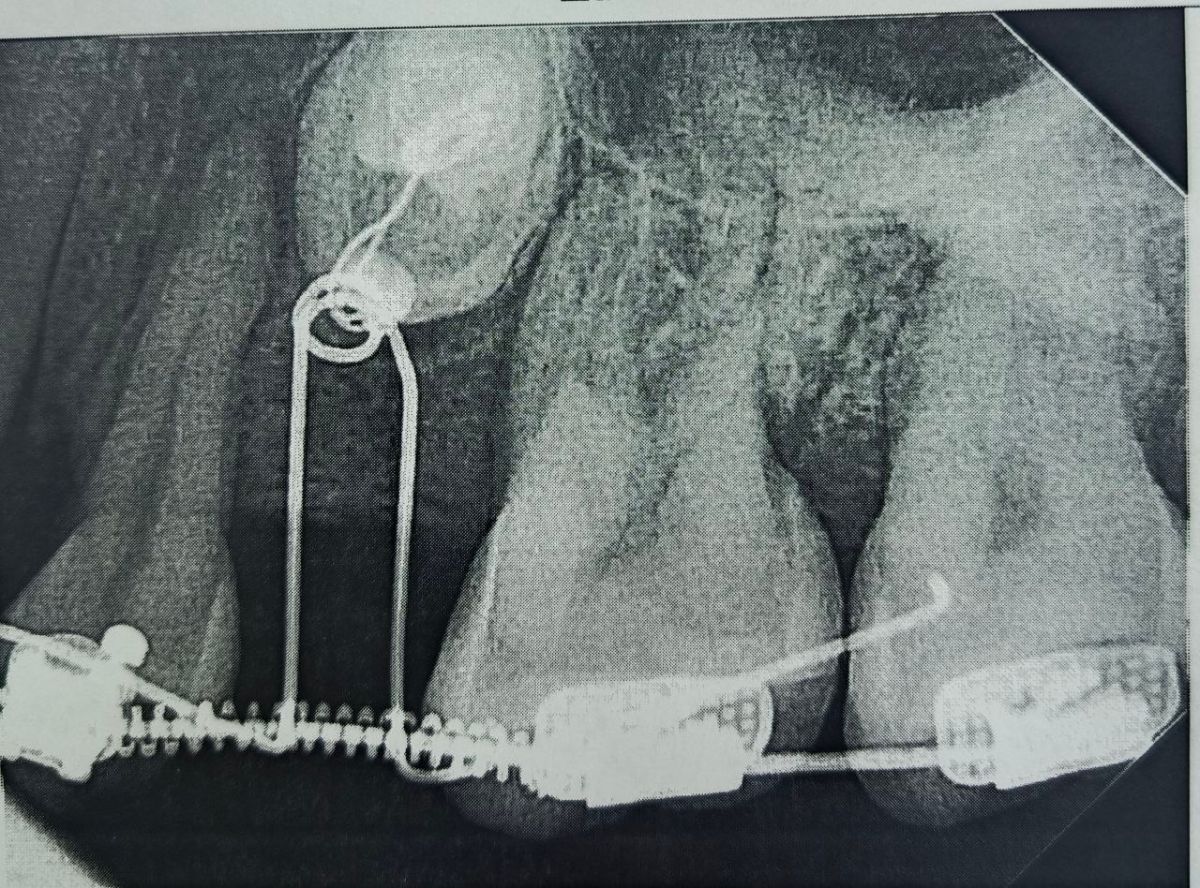

Воронежские стоматологи успешно проводят сложное ортодонтическое лечение, возвращая в зубной ряд два непрорезавшихся зуба у 38-летней женщины. Лечение, начавшееся еще в 2023 году, уже показывает впечатляющие результаты. Об этом сообщила пресс-служба областного Минздрава.

Пациентка обратилась в областную стоматологическую поликлинику с редкой проблемой: два зуба так и не прорезались и остались в костной ткани. Компьютерная томография показала их точное расположение. Поскольку у женщины к тому же отсутствовал один зуб, а другой был аномально маленьким, врачи приняли нестандартное решение — не удалять «спрятанные» зубы, а попытаться вытянуть их на законное место.

Процесс потребовал ювелирной работы и терпения. Сначала с помощью брекетов в течение полутора лет создавалось необходимое пространство. Затем хирургическим путём открыли доступ к коронкам непрорезавшихся зубов и закрепили на них специальные ортодонтические кнопки. С помощью системы рычагов и пружин один зуб уже удалось вывести из челюсти, а второй сейчас находится в процессе прорезывания.